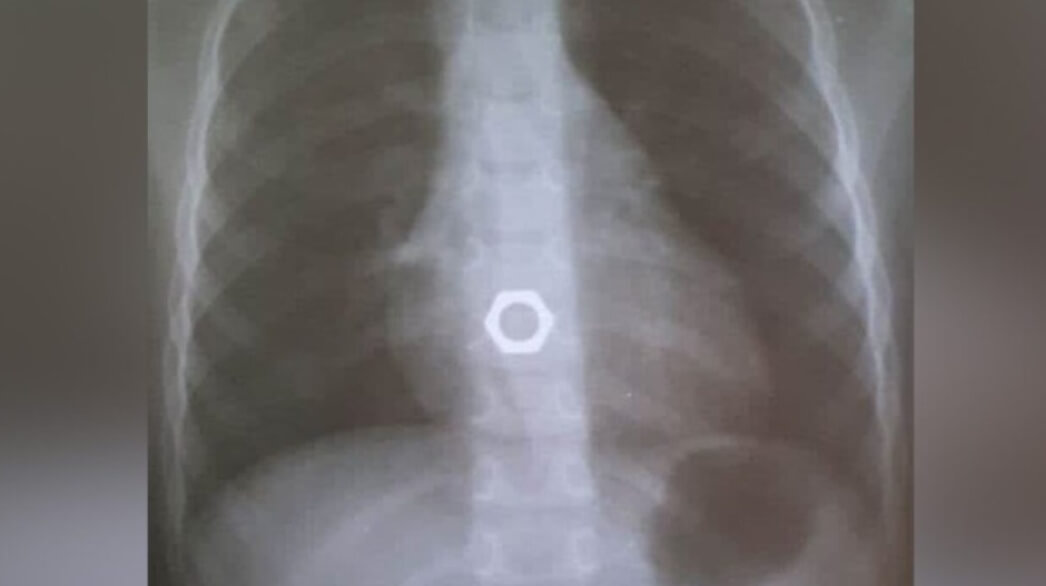

Ожидается, что робот сможет извлекать из организмов инородные предметы

Но технология для извлечения инородных предметов из организма человечеству нужна. Некоторые люди, особенно маленькие дети, иногда случайно проглатывают опасные предметы. В 2014 году на страницах научного издания LiveScience появилось сообщение о том, что в мире очень часты случаи проглатывания детьми магнитных шариков. Из-за этого игрушки с небольшими магнитами в США на некоторое время были запрещены, а после снятия запрета количество госпитализаций по поводу их проглатывания увеличилось на целых 400%. Опасность проглатывания магнитов заключается не только в их токсичности. Внутри организма они могут притянуться и блокировать жизненно важные пути.